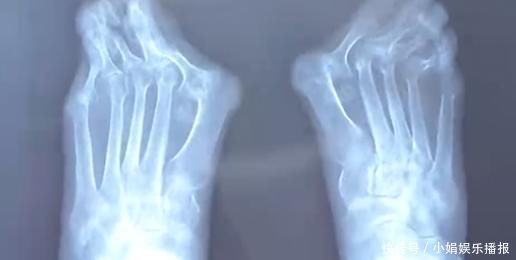

由于高跟鞋的挤压,王女士的左脚大脚趾变成了两个脚趾,随着时间的推移,大脚趾一侧又多了一个 \\'\\'拐\\'\\',现在只能通过手术来缓解症状。除了鞋子不当,遗传和疾病因素也是造成拇指外翻的原因,70 岁的高女士患风湿病,脚也发生了接近 60 度的严重变形。

忍痛十几年,直到前几天,高女士连男士的鞋子都穿不上,眼看着不能走路了才来到医院就诊,而这时手术的风险和难度都增大很多。